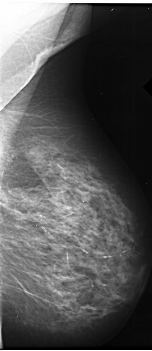

A_1019_1.LEFT_CC

LEFT_CC LINES 5821 PIXELS_PER_LINE 3331 BITS_PER_PIXEL 16 RESOLUTION 42 OVERLAY